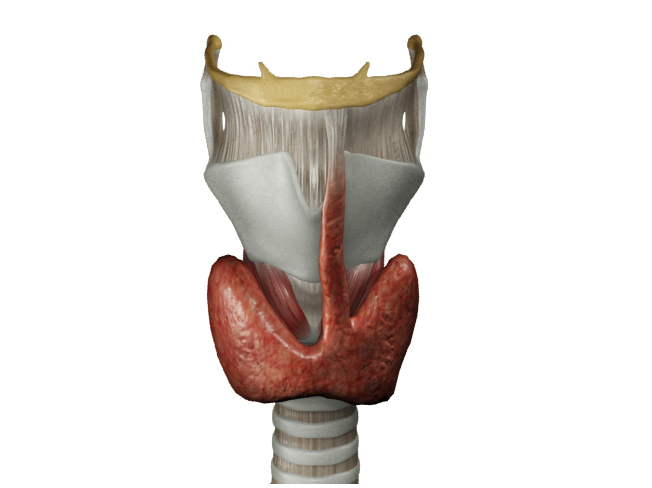

홍보, 학회 발표, 수술 교육, 의학 제품 소개와 관련한 영상을 3D로 제작하여 제공해드립니다.

제작범위 : 신체 전신, 뼈대, 장기, 혈관 등 사람, 동물의 모든 표현이 가능하며, 수술과 관련한 도구 제작도 가능합니다.